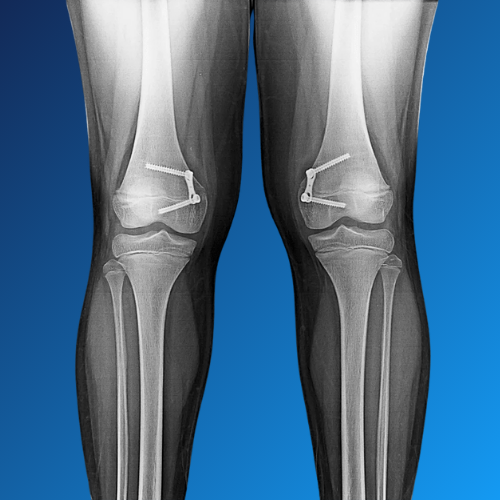

Orthopaedic deformities can affect bones, joints, or limbs — leading to pain, limited mobility, and difficulty in daily activities. These may be congenital (by birth), developmental, or the result of trauma, disease, or previous surgery. Dr. Nishant Bhatia offers expert evaluation and surgical correction of bone and joint deformities using advanced techniques and personalized care.

• Growth modulation in children (minimally invasive)

• Osteotomy and realignment surgeries in adults

• Use of internal fixation, plates, or external fixators